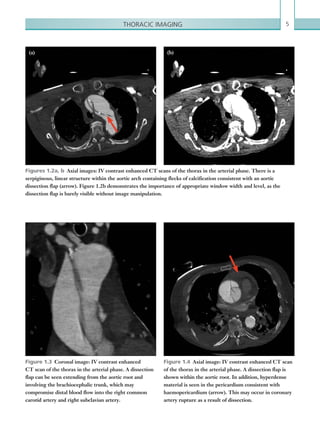

Figures 1.2a, b  Axial images: IV contrast enhanced CT scans of the thorax in the arterial phase. There is a

serpiginous, linear structure within the aortic arch containing flecks of calcification consistent with an aortic

dissection flap (arrow). Figure 1.2b demonstrates the importance of appropriate window width and level, as the

dissection flap is barely visible without image manipulation.

(a) (b)

Figure 1.3  Coronal image: IV contrast enhanced

CT scan of the thorax in the arterial phase. A dissection

flap can be seen extending from the aortic root and

involving the brachiocephalic trunk, which may

compromise distal blood flow into the right common

carotid artery and right subclavian artery.

Figure 1.4  Axial image: IV contrast enhanced CT scan

of the thorax in the arterial phase. A dissection flap is

shown within the aortic root. In addition, hyperdense

material is seen in the pericardium consistent with

haemopericardium (arrow). This may occur in coronary

artery rupture as a result of dissection.